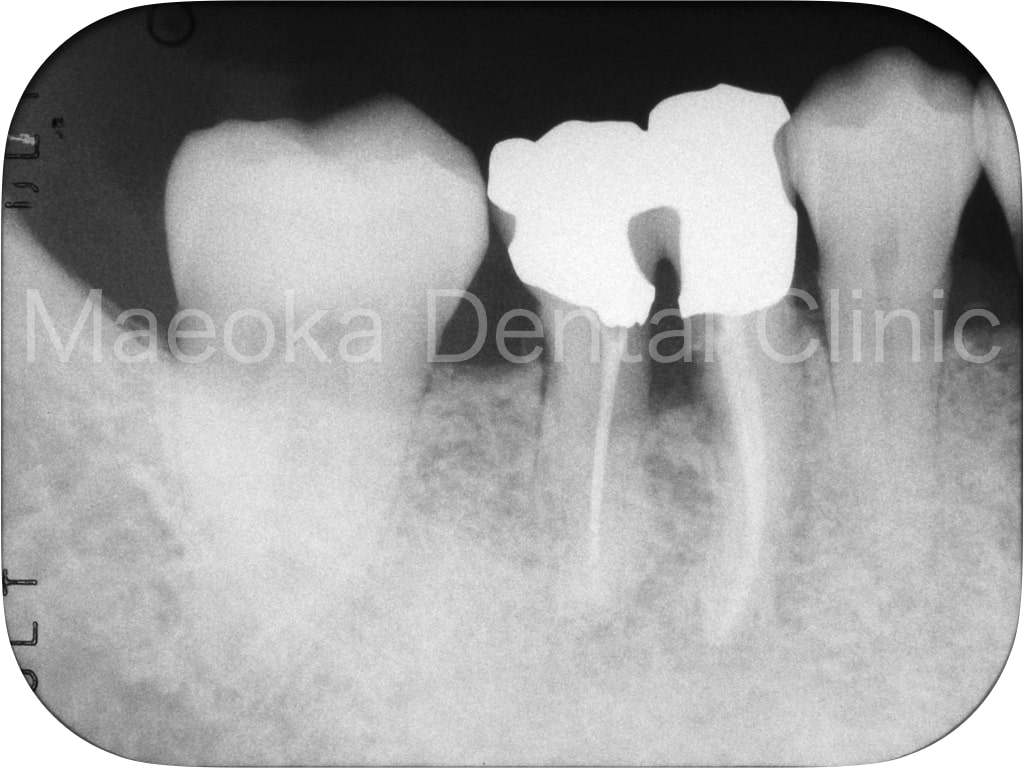

患者さんは58歳の男性の方で、「右下の歯がグラグラして痛いので診て欲しい」という主訴で来院されました。お口の中を拝見すると重度の歯周病を認めました。1日1箱近い本数の喫煙があったこともあり、歯肉は血行不良を起こして黒っぽい印象がありました。

初診時には歯周病の原因と「どうすれば歯周病は治るのか」、「再発を防ぐためには何が必要なのか」を説明し、歯磨きのトレーニングをスタートしました。その後、患者さんのプラークコントロールレベルが向上したタイミングで歯石を取り、基本治療を終えました。その後、義歯を入れるなどの機能回復も検討しましたが、患者さん自身が不都合を感じていなかった点、レントゲン上でも残存歯の負担が増加している所見が見られなかった点を考慮し、経過観察としています。

主訴の右下7は失うことになってしまいましたが、その他の歯は現在のところ1本も失うことなく経過しています。現在も喫煙はありますが、歯肉は引き締まり、健康な組織を取り戻しています。今後はメインテナンスを通してプラークコントロールレベルの維持に患者さんと取り組んでいきます。

初診時の右下大臼歯部

治療前(正面)

治療後(正面)